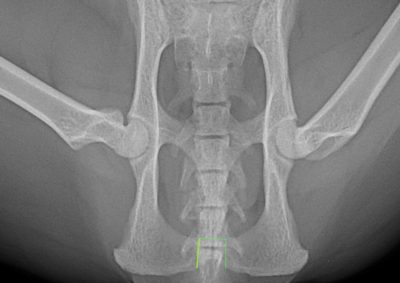

会陰尿道瘻設置術後の狭窄に対する坐骨骨切り尿道瘻設置術